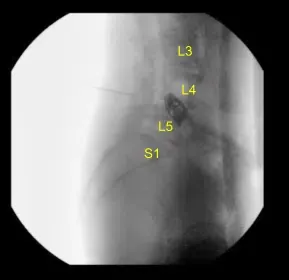

La región lumbar se preparó y colocó de forma estéril habitual y luego se utilizó una fluoroscopia para localizar nuestra incisión, que se trazó con un marcador imborrable en la línea media de la región lumbar que cubre el interespacio L4-L5. Se administraron antibióticos intravenosos y se completó una llamada por orden.

Extirpamos el tejido blando del hueso de forma no traumática y luego aplicamos el sistema de separador McCullough. Luego se usaron los separadores Gelpi de ángulo recto para separar los bordes de piel y músculo. Usamos fluoroscopia una vez más para localizar nuestro nivel de operación.

Dada la preocupación por el implante en posición prona y la sensación de que las placas terminales podrían haberse fracturado más, expusimos los procesos transversales de L4 y L5 y usamos el taladro para crear agujeros piloto en el pedículo del lado izquierdo en L4 y L5. Bajo fluoroscopia, guiamos las sondas a través de los pedículos y tocamos cada pedículo, luego colocamos tornillos pediculares en L4 y L5.